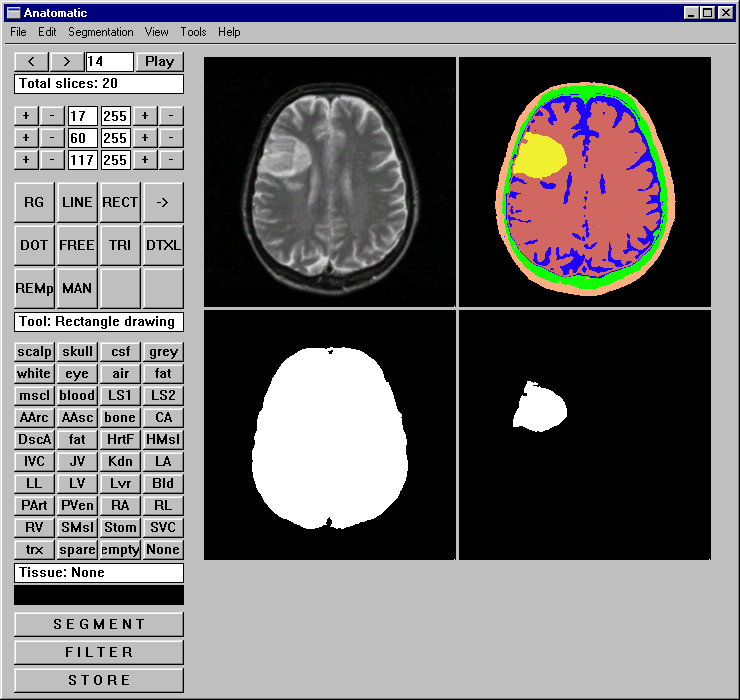

Segmentation is a third alternative e.g. to separate white matter from gray matter or ventricles (CSF space).

Brain image segmentation is especially well suited for this type of an approach.

We in Tampere have developed a different type of an approach. The original digital neurotlas is transferred

on the corresponding sections of the MRI image of the patient The shape and size of the neuroatlas can be modified

by using different mathematical algorithms (rubber sheet and wrap algorithms). Also the possible errors in the

patient image (rotations, translations and stretching) can be corrected (Lahtinen A et al 1998). Some of the neuroatlases,